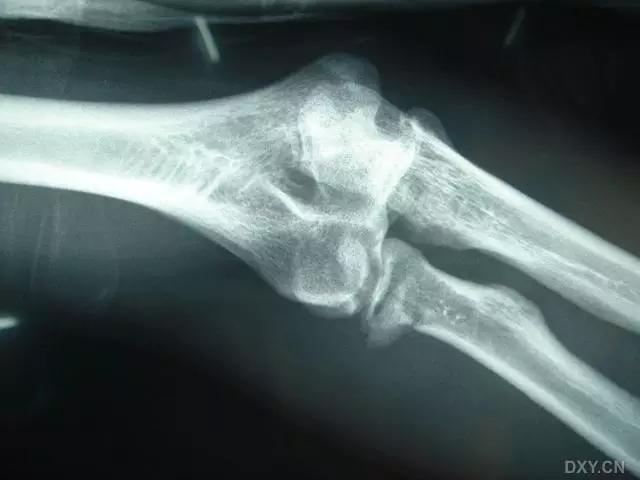

5. Hoffa 骨折

指股骨远端冠状面的骨折。

病例 1:一般股骨髁间、髁上粉碎骨折中含 Hoffa 骨折的不少见,但单纯后髁骨折则很少见。

正位片

侧位片

水平位 CT

第 2 例

第 3 例